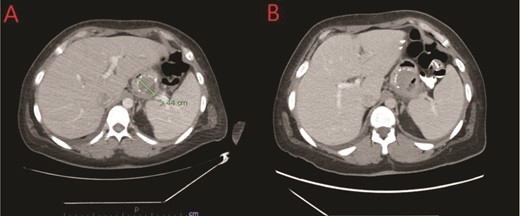

We report a case of a 39-year-old female, with a past medical history significant for morbid obesity status-post SADI-S ⁓3 years prior at an out-of-state medical center who was transferred to our institution with computed tomography (CT) evidence of an intramural abscess near the proximal greater curvature of the stomach as displayed in Fig. 1A. Our patient had a reported weight loss of 99.8 kg since her bariatric surgery and did not encounter any significant issues until this current episode of symptoms began. She was previously treated with a 2-week course of intravenous (IV) antibiotics with minimal symptomatic improvement prior to transfer to our facility. Notably, the patient was treated with oral corticosteroids ⁓1 month before she initially presented to the hospital for a streptococcal infection. She reported being a non-smoker (neither currently nor previously) and also denied recent use of NSAIDs or proton pump inhibitors (PPIs).

(A) CT showing a complex fluid collection at the proximal greater curvature of the stomach consistent with intramural abscess. (B) Interval improvement in complex fluid collection after endoscopic stent removal.

The patient’s postprocedure course was complicated with severe epigastric abdominal pain, resulting in repeat EGD and stent removal seven days after placement. A follow up CT was completed which demonstrated improvement in the complex fluid collection as shown in Fig. 1B. Her diet was advanced and the patient was tolerating a full liquid diet by the date of her discharge.